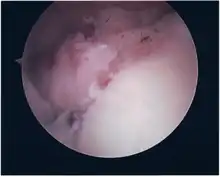

Procedure

Following inspection and determination of the extent of injury, the basic labrum repair is as follows.

- The glenoid and labrum are roughened to increase contact surface area and promote re-growth.

- Locations for the bone anchors are selected based on number and severity of tear. A severe tear involving both SLAP and Bankart lesions may require seven anchors. Simple tears may only require one.

- The glenoid is drilled for the anchor implantation.

- Anchors are inserted in the glenoid.

- The suture component of the implant is tied through the labrum and knotted such that the labrum is in tight contact with the glenoid surface.